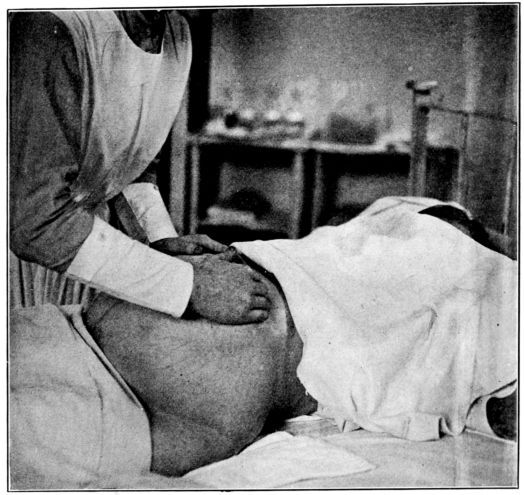

| 57. | First maneuver in abdominal palpation | 225 |

| 58. | Second maneuver in abdominal palpation | 226 |

| 59. | Third maneuver in abdominal palpation | 227 |

| 60. | Fourth maneuver in abdominal palpation | 228 |

| 61. | Diagrams showing positions of nurse’s hands in four maneuvers of abdominal palpation | 229 |